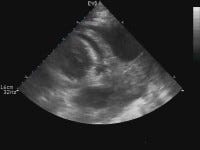

From Philippe Rola and the Critical Care & Ultrasound Institute, the first in a series of educational ultrasound cases on PulmCCM: A 64 year-old male is admitted to the ICU from the surgical ward with hypotension, 3 days post-cholecystectomy. He is intubated for airway protection following loss of consciousness with systolic BP in the 60’s. Past medical history includes hypertension, diabetes, coronary artery disease, and atrial fibrillation. His surgery was uncomplicated. Medications include ciprofloxacin, metronidazole, metoprolol, ASA, atorvastatin, amlodipine and enoxaparin. The patient looks unwell, pale, and is sedated, intubated, and mechanically ventilated. Chest is clear without wheezing and with good air entry bilaterally. Heart sounds irregular without significant murmurs or rubs, and no jugular venous distension noted. Abdominal exam reveals some distension but without rigidity. Bowel sounds are faint, and some mild tenderness around laparoscopic sites but otherwise no pain on palpation. No masses are felt. Skin is cool with some livedo around the knees. EKG shows rapid atrial fibrillation without ischemic changes. Current laboratory tests are pending, those from the morning are within acceptable ranges.

ULTRASOUND VIDEOS (3):